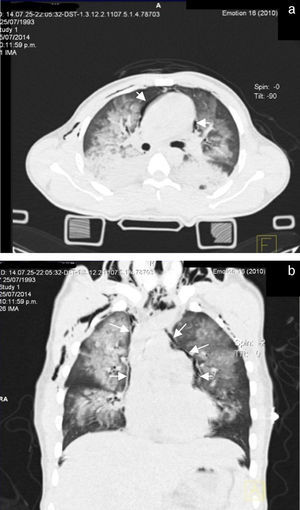

It was decided to refer the patient to the Maxillofacial Department for surgery, 48h after admission, for open reduction internal fixation of the alveolopalatal fracture. During the immediate postoperative period he went into respiratory failure, underwent orotracheal intubation for mechanical ventilation support, and was sent to the intensive care unit. A repeat chest X-ray was performed which revealed the presence of multiple bilateral infiltrates associated with pulmonary contusion and an image suggestive of pneumopericardium (Fig. 1).

Seventy-two hours after admission, the patient presented subcutaneous emphysema in the anterior chest extending to the neck, a simple CT scan was performed of the chest and abdomen which revealed a pneumomediastinum, bilateral lung contusions and pneumoperitoneum (Figs. 2 and 3). He continued on mechanical ventilation. Oesophageal injury was ruled out by oesophagogram with water-soluble contrast medium, and flexible bronchoscopy ruled out tracheobronchial injury. Furthermore, no signs of peritoneal irritation were found, therefore the Macklin effect was established as the cause of the pneumomediastinum and pneumoperitoneum.

In the event that a pneumomediastinum is suspected, the initial laboratory study is frontal and lateral chest X-ray, including the cervical region; this study will reveal the pneumomediastinum in 90% of cases.9 The radiographic signs suggestive of a pneumomediastinum include a radiolucent line which outlines the mediastinal structures (most evident cranial to heart on the left side), lifts the mediastinal pleura and often extends to the neck or the chest wall. On a lateral projection, this radiolucent line can outline the aortic arch, the retrosternal, precardiac, periaortic and peritracheal areas. Other radiographic signs include “continuous diaphragm sign”, which is mediastinal gas outlining the upper surface of the diaphragm and separating it from the heart; “Naclerio's V sign”, which presents gas outlining the lateral edge of the descending aorta and which extends laterally between the parietal pleura and the medial portion of the left hemidiaphragm, and the “ring around the artery sign” where the gas surrounds the mediastinal extrapericardial portion of the right pulmonary artery.10,13

Indirect radiographic signs include thoracic and cervical subcutaneous emphysema, pneumopericardium, pneumoretroperitoneum and pneumoperitoneum. The presence of a pneumothorax should be deliberately sought; this can be present in 84% of patients. The presence of a penumothorax in patients with pneumomediastinum does not necessarily indicate injury to an organ of the mediastinum; in fact it is a strong negative indicator of oesophageal injury or association with injury to the airway.10 In the clinical case that we present, there was evidence of pneumomediastinum associated with a pneumothorax, with no demonstrated oesophageal or airway injury.